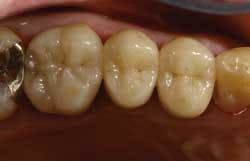

From the very first three units I cemented, I knew there was something special about the Wol-Ceram system. These were the first all-ceramic crowns I had ever inserted that felt like PFMs as they slid down into place. There is nothing quite so reassuring as being able to feel the mechanical retention of a crown as it moves down the prep.

I still prefer to cement rather than bond, and Wol-Ceram can be cemented with any crown and bridge cement of your choice. The next time you have a need for an all-ceramic crown that preps, fits, cements, and costs the same as a PFM, give Wol-Ceram a try.